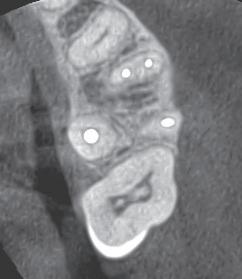

A 60-year-old female patient presented to the Oklahoma University College of Dentistry with the chief complaint, “My dogs chewed up my lower denture, and I need a replacement” (Figure 8a). Clinical examination revealed a completely edentulous oral cavity with advanced resorption of the mandibular alveolar ridge (Figure 1a and 1b). Based on panoramic radiographic ndings and nancial considerations, an implant-supported complete denture was determined to be impractical (Figure 2). A treatment plan was proposed involving the fabrication of a conventional maxillary complete denture and a mandibular complete denture using the neutral zone technique. As the maxillary denture was fabricated using conventional techniques, this report will primarily

Figure 2. Panoramic radiograph